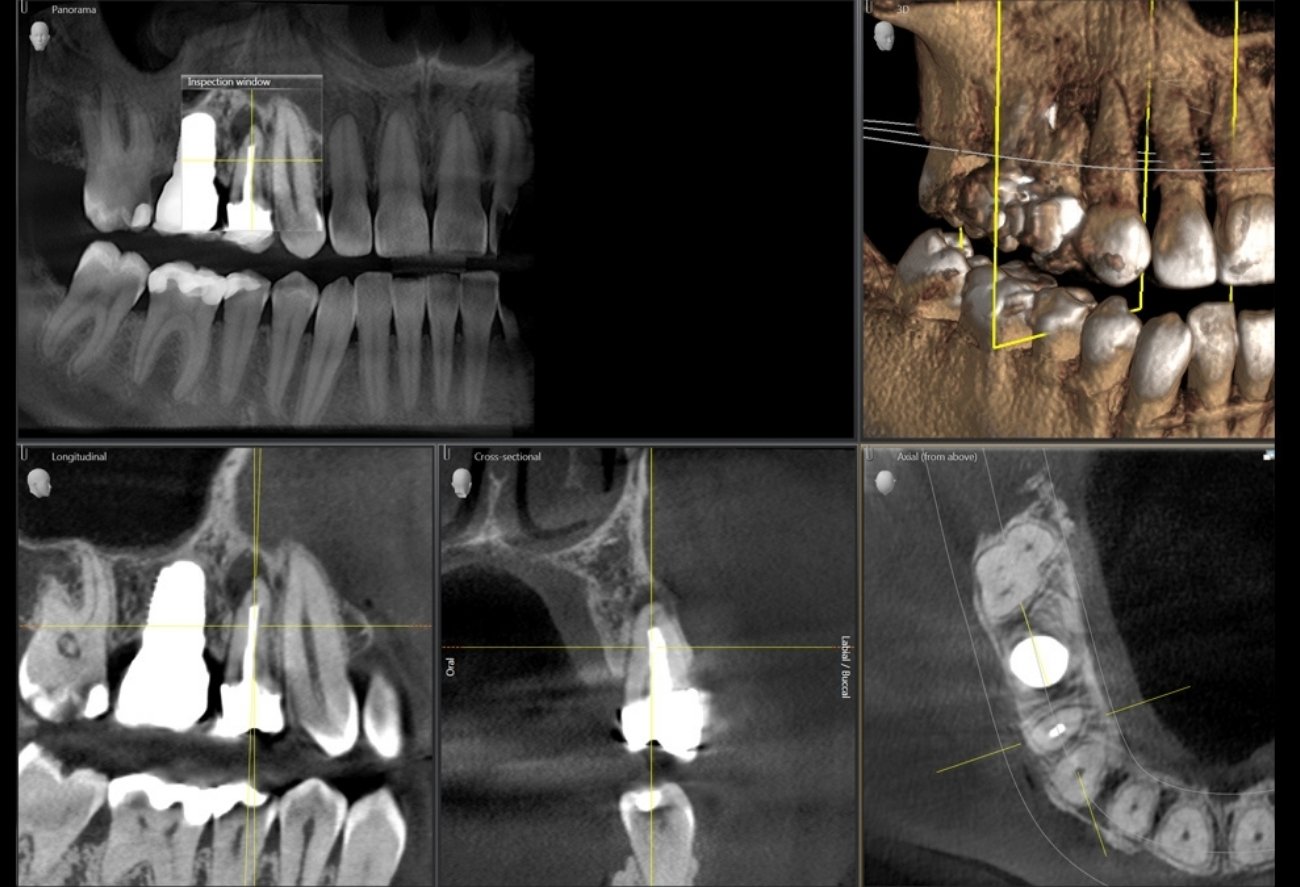

Приклади 3D-зображень: